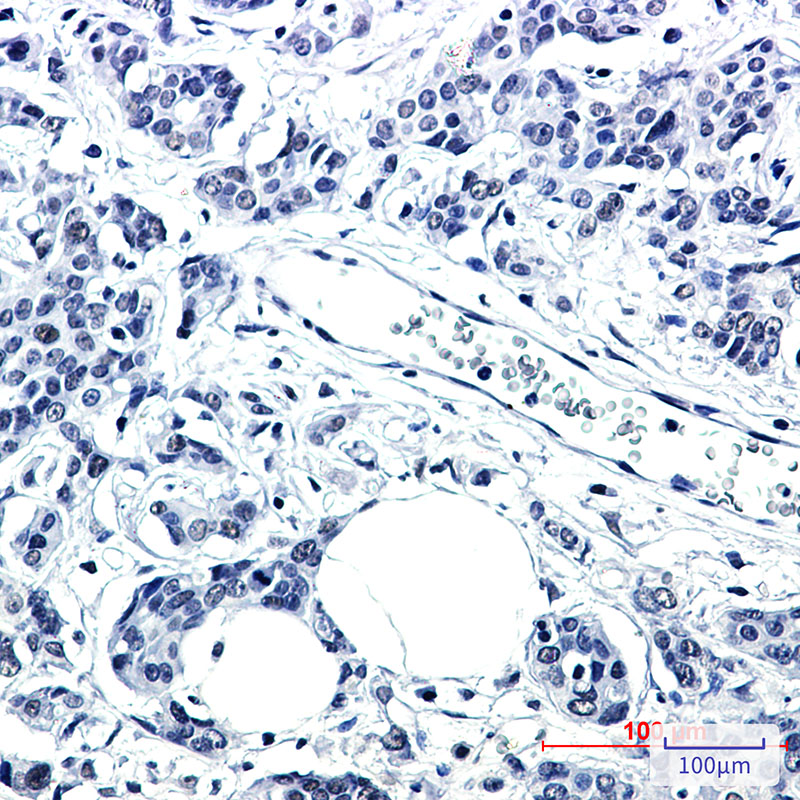

分类: 科研抗体货号: P22501别名: TMEM142C应用: WB,IHC反应种属: Human